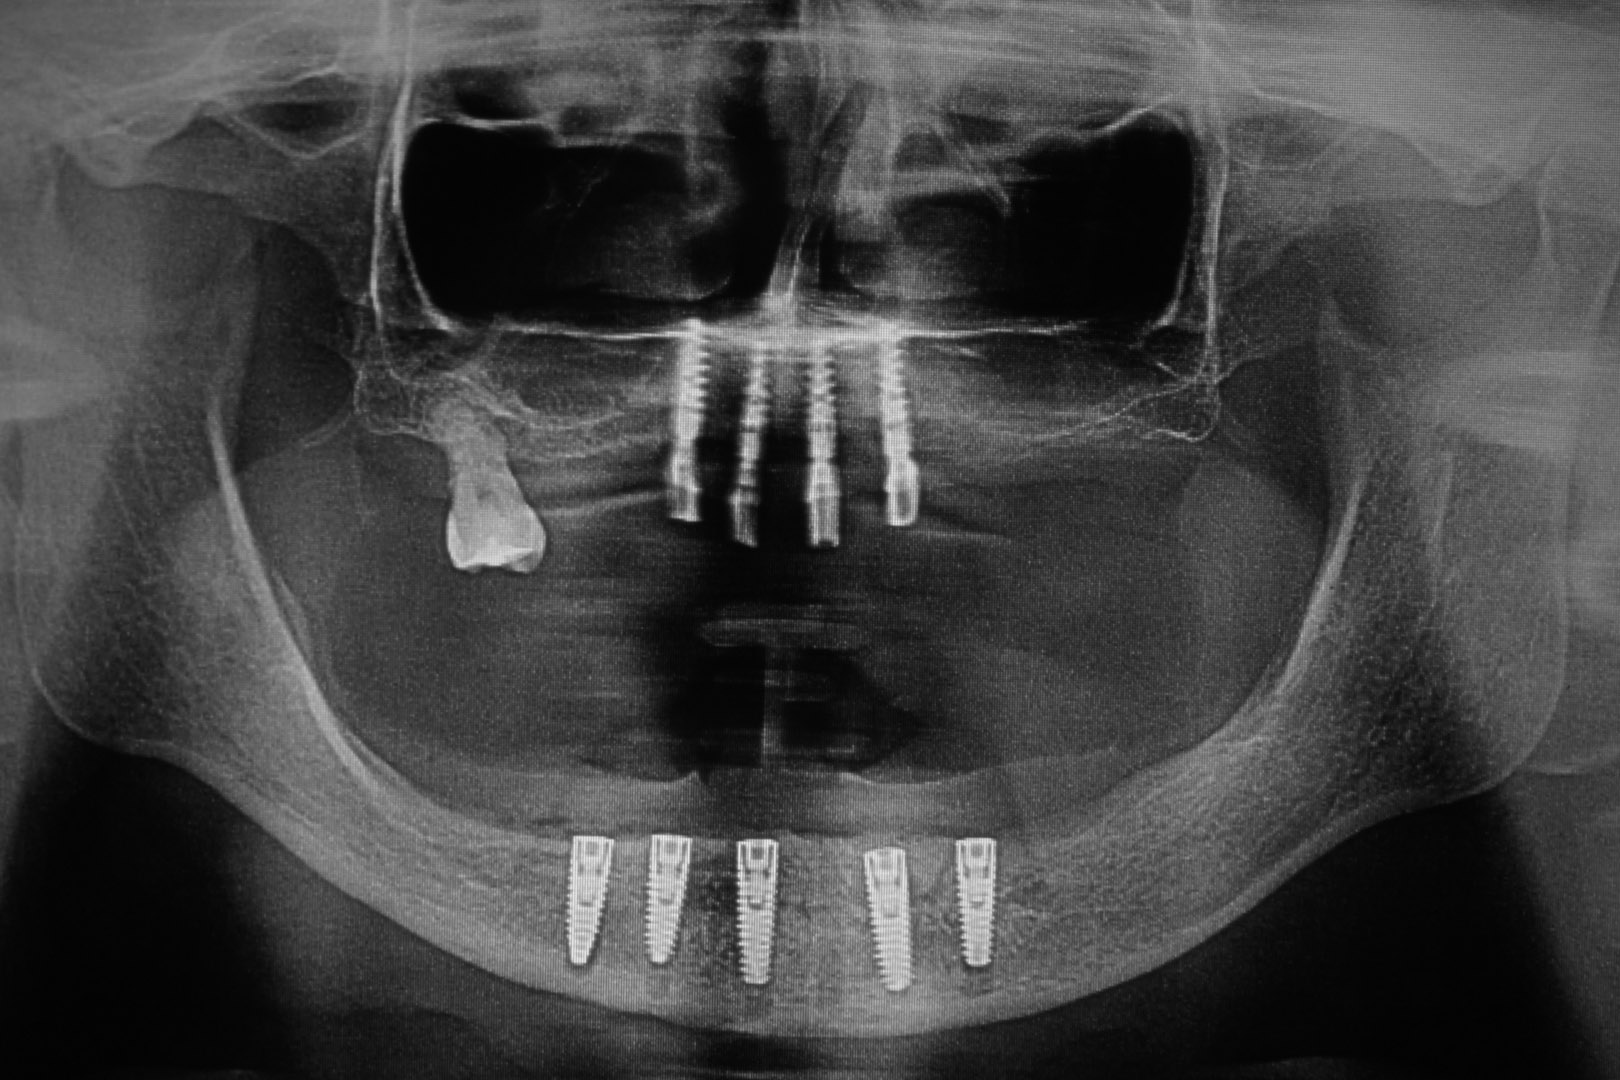

Nie ma takiej konieczności. Z biologicznego punktu widzenia jest to nawet niewskazane. Regułą i standardem w odbudowie protetycznej uzębienia jest rekonstrukcja górnego, jak i dolnego łuku zębowego od pierwszego trzonowca po stronie prawej do pierwszego zęba trzonowego po stronie lewej. W oparciu o diagnostykę obrazową (OPG, CBCT) standardowo oceniamy jakość i objętość kości oraz planujemy leczenie, bazując na prognozowanej ilości wszczepianych implantów. W zależności od zaplanowanych rozwiązań protetycznych ich ilość zwykle waha się od dwóch do dziesięciu implantów jako fundament dla rekonstrukcji uzębienia górnego lub dolnego łuku zębowego.

Dla szczęk, czyli łuku górnego, stosujemy:

– charakterystyczne dla anatomii szczęk zabiegi rekonstrukcyjne typu podniesienie dna zatoki szczękowej lub dna nosa oraz pozostałe uniwersalne techniki rekonstrukcyjne umożliwiające wszczepienie implantów zębowych o standardowych rozmiarach

– rozwiązania Overdenture na 2–4 implantach

– krótkie implanty o długości mniejszej niż 10 mm dla stref bocznych

– rozwiązania All-on – 4 All-on – 6

– system rozwiązań oparty na implantach jarzmowych Zygoma

Dla żuchwy, czyli łuku dolnego, stosujemy:

– charakterystyczne dla anatomii żuchwy zabiegi rekonstrukcyjne typu transpozycja nerwu zębodołowego dolnego oraz pozostałe uniwersalne techniki rekonstrukcyjne umożliwiające wszczepienie implantów zębowych o standardowych rozmiarach

– krótkie implanty o mniejszej długości niż 10 mm dla stref bocznych

Jest to opatentowana metoda rekonstrukcji implanto-protetycznej kompletnego uzębienia stosowana przy bezzębiu zarówno dla dolnego, jak i górnego łuku zębowego. Bazuje na charakterystycznie wszczepionych 4 implantach zębowych, stąd nazwa Wszystko na 4. Dwa środkowe wprowadzane są w kość prostopadle do jej brzegu i równolegle do siebie, dwa boczne wszczepiane są pod kątem 45 stopni. Rozwiązanie protetyczne to most przykręcany na stałe do implantów, który może być zakładany natychmiast po zabiegu implantacji lub w czasie odroczonym. Gwarancją natychmiastowego przywrócenia funkcji żucia jest odpowiednia siła osadzania implantów mierzona dynamometrycznie w trakcie ich wszczepiania oraz należyta staranność wykonania i osadzenia prac protetycznych.

Po ekstrakcji zębów w zakresie górnego łuku zębowego najszybciej zanika kość w strefach bocznych, czyli w okolicy zębów trzonowych, najpóźniej w odcinku przednim, czyli w strefie zębów siecznych.

W zależności od stadium zaniku kostnego mamy różne możliwości implantacji oraz odbudowy kostnej. W ślad za możliwościami implantologicznymi idą rozwiązania protetyczne mniej lub bardziej komfortowe dla pacjenta. Za komfortowe, tym samym optymalne, uznaje się te, które są na stałe montowane na implantach. O możliwości ich zastosowania decyduje rodzaj zastosowanych implantów, ich ilość i rozmiary, siła, z jaką są posadowione w kości, jakość, wymiary oraz fakt, czy była odbudowywana czy tego nie wymagała.

W sytuacji rozległych zaników kostnych górnego łuku optymalnym, czyli szybko działającym i przewidywalnym rozwiązaniem jest zastosowanie implantów jarzmowych Zygoma, które jako jedyne w sytuacji skrajnie trudnych warunków kostnych dają możliwość odbudowy protetycznej w formie mostów montowanych na stałe na implantach.